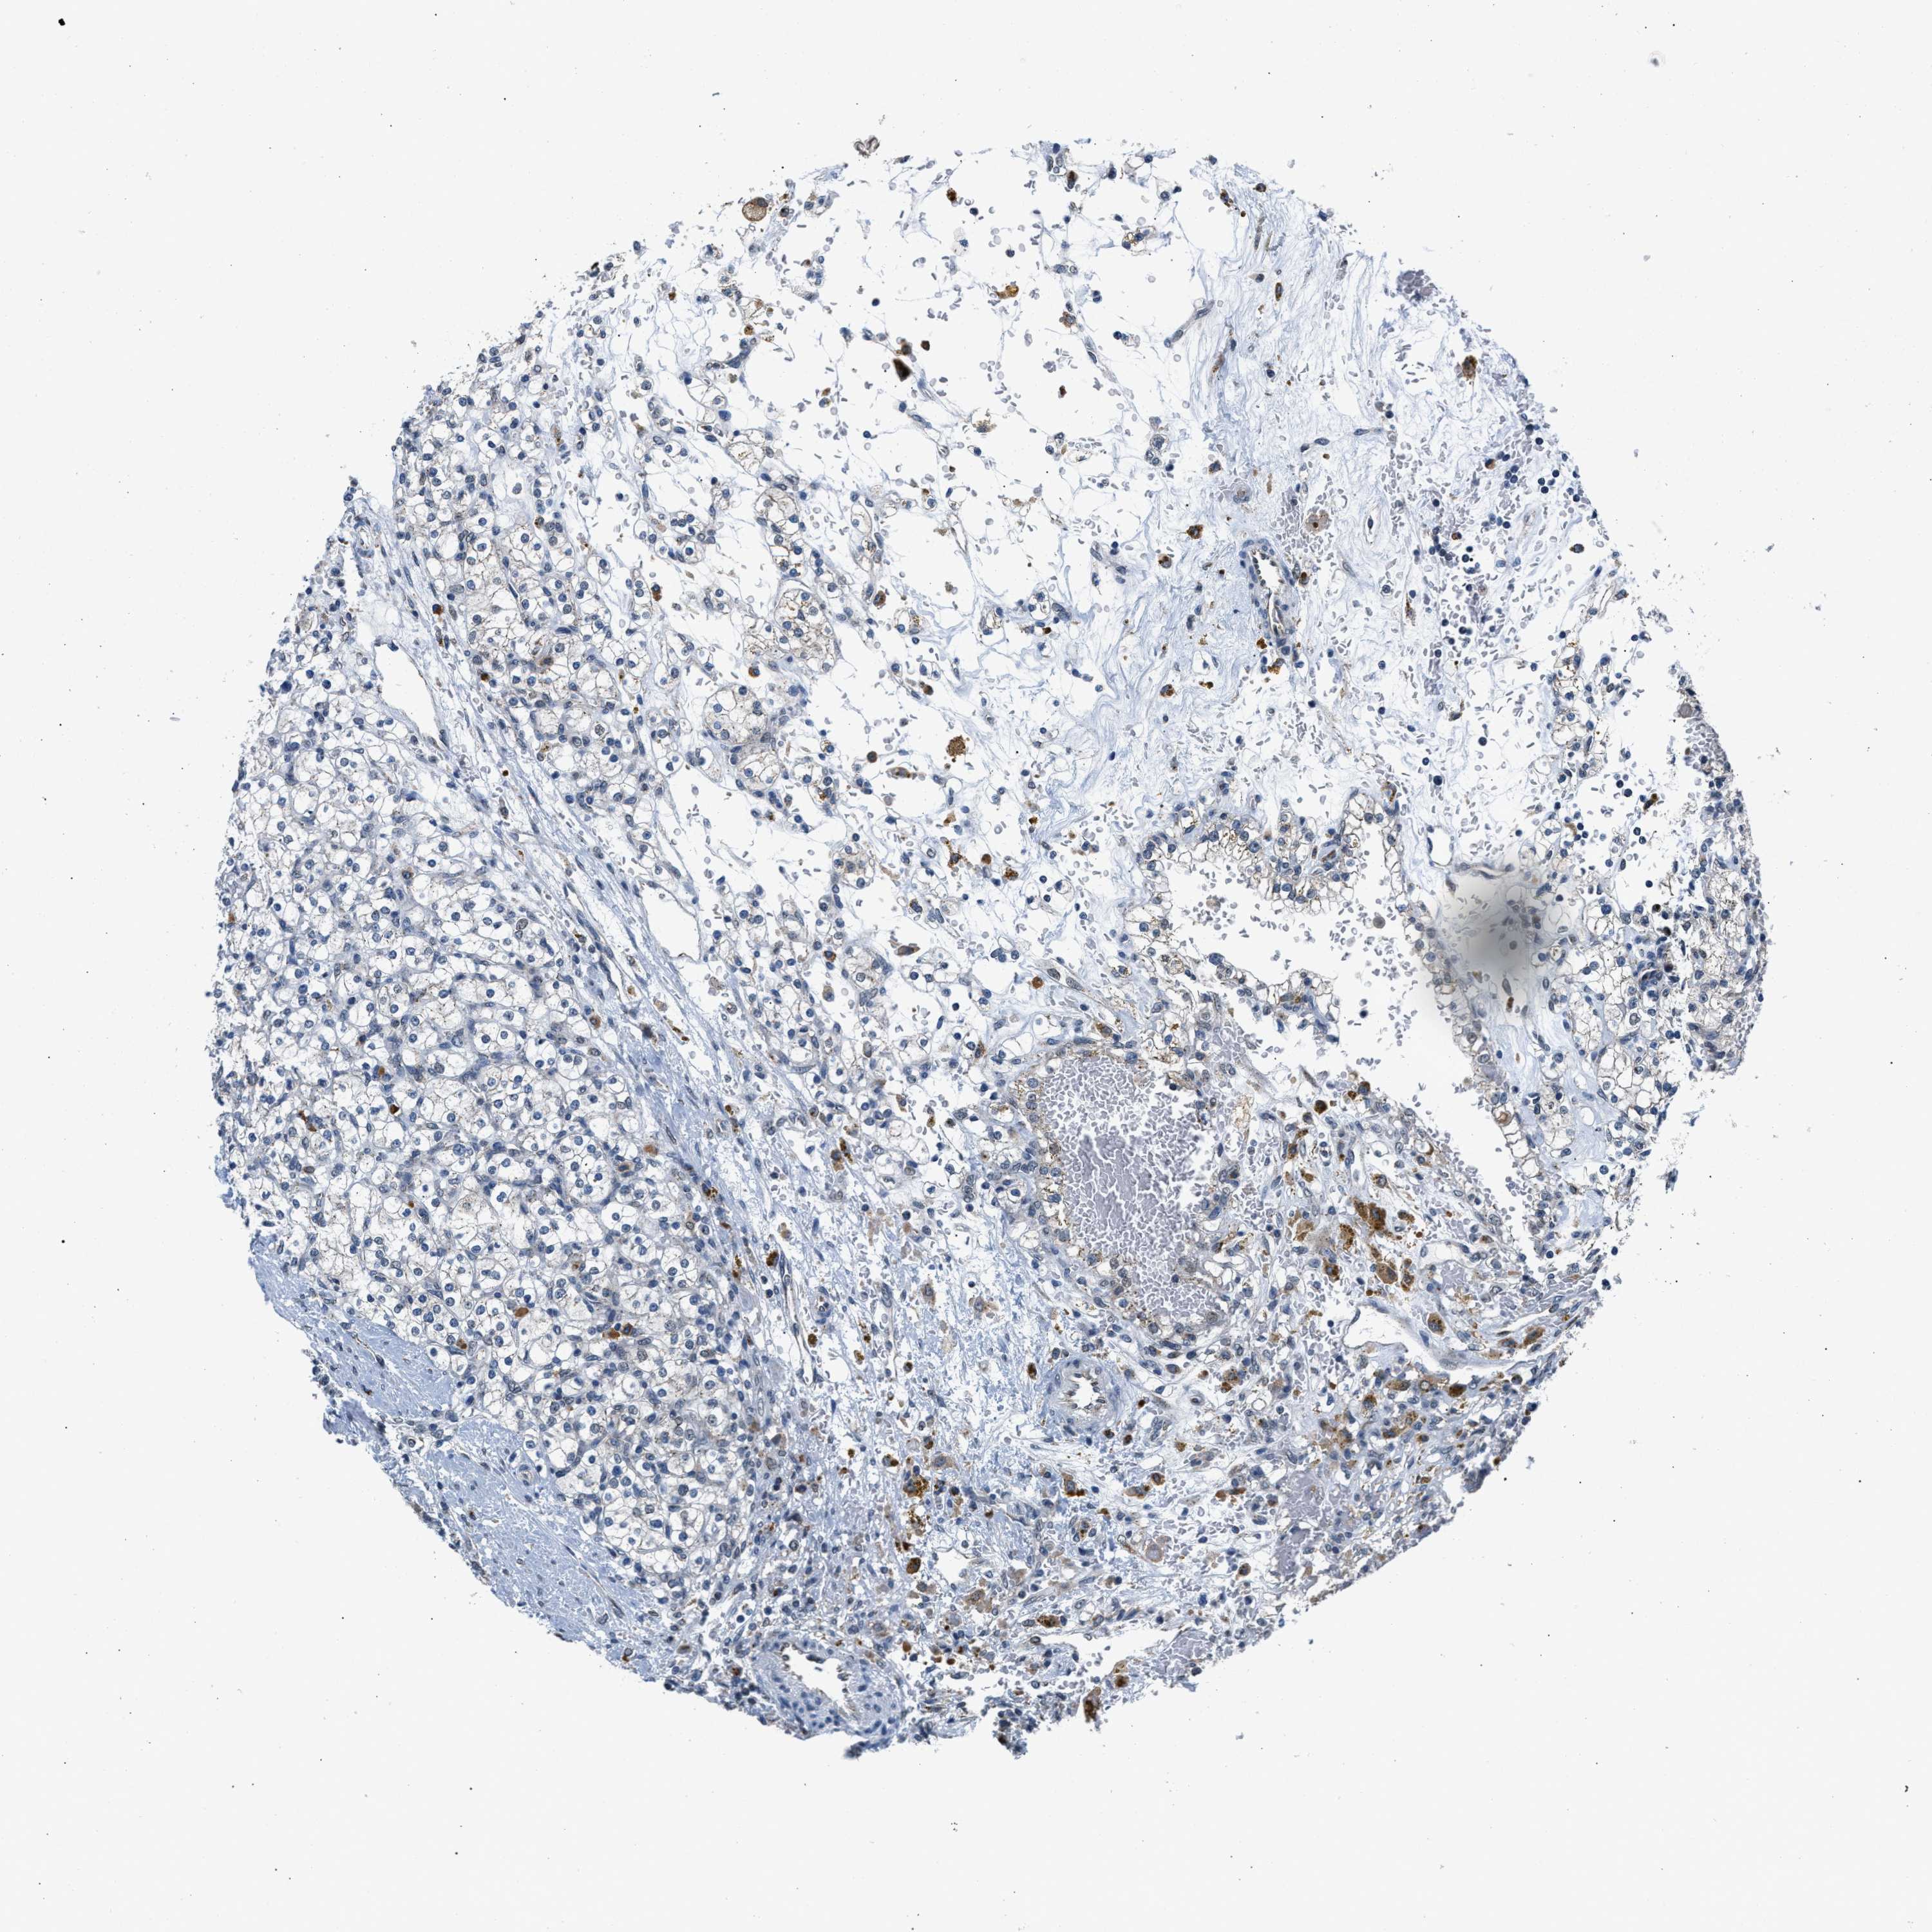

KIDNEY RENAL PAPILLARY CELL CARCINOMA (TCGA) - Interactive survival scatter ploti

The Survival Scatter plot shows the clinical status (i.e. dead or alive) for all individuals in the patient cohort, based on the same data that underlies the corresponding Kaplan-Meier plots. Patients that are alive at last time for follow-up are shown in blue and patients who have died during the study are shown in red.

The x-axis shows the expression levels (FPKM) of the investigated gene in the tumor tissue at the time of diagnosis. The y-axis shows the follow-up time after diagnosis (years). Both axes are complimented with kernel density curves demonstrating the data density over the axes. The top density plot shows the expression levels (FPKM) distribution among dead (red) and alive patients (blue). The right density plot shows the data density of the survived years of dead patients with high and low expression levels respectively, stratified using the cutoff indicated by the vertical dashed line through the Survival Scatter plot. This cutoff is automatically defined based on the FPKM cutoff that minimizes the p-score. The cutoff can be changed by dragging the vertical line or by entering a cutoff value in the square labeled "Current cut-off".

Under the Survival Scatter plot the p-score landscape (black curve; left axis) is shown together with dead median separation (red curve; right axis). Dead median separation is the difference in median mRNA expression between patients who have died with high and low expression, respectively. It is calculated as follows: median FPKM expression of dead patients with high expression - median FPKM expression of dead patients with low expression. This is intended to aid the user in visually exploring custom cutoffs and the associated p-scores and dead median separation.

Individual patient data is displayed and can be filtered by clicking on one or more of the category buttons on the top of the page. Categories describing expression level and patient information include: high, low, alive, dead, female, male and tumor stages. The scale of the x-axis can be toggled between linear and log-scale by clicking on the "x log" button. Mouse-over function shows TCGA ID, patient information and mRNA expression (FPKM) for each patient.

& Survival analysisi

Kaplan-Meier plots summarize results from analysis of correlation between mRNA expression level and patient survival. Patients were divided based on level of expression into one of the two groups "low" (under cut off) or "high" (over cut off). X-axis shows time for survival (years) and y-axis shows the probability of survival, where 1.0 corresponds to 100 percent.

KCNMB2 is not prognostic in Kidney Renal Papillary Cell Carcinoma (TCGA)